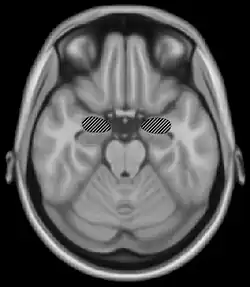

Amygdala

The amygdala.

Located above the hippocampus in the medial temporal lobes are two amygdalae (singular "amygdala"). The amygdalae are associated with both emotional learning and memory, as it responds strongly to emotional stimuli, especially fear. These neurons assist in encoding emotional memories and enhancing them. This process results in emotional events being more deeply and accurately encoded into memory. Lesions to the amygdalae in monkeys have been shown to impair motivation, as well as the processing of emotions.[5]